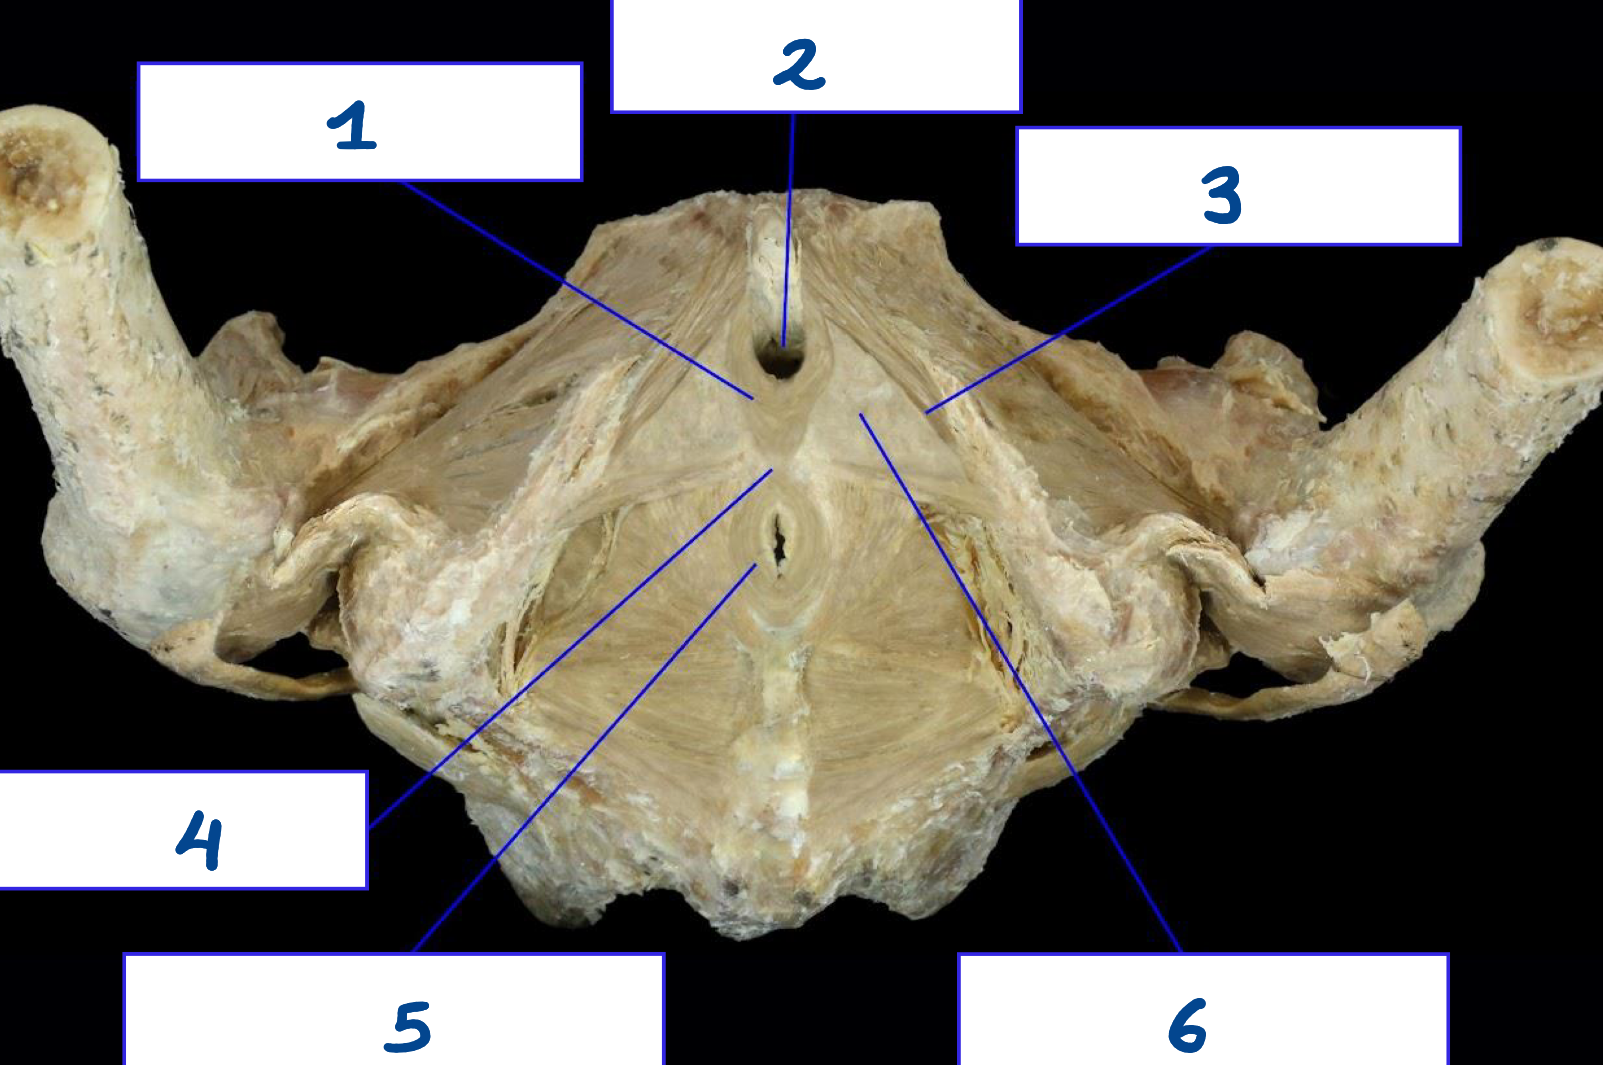

<p>What is structure 1?</p>

What is structure 1?

Urogenital triangle

<p>What is structure 2?</p>

What is structure 2?

Pubic symphysis

<p>What is structure 3?</p>

What is structure 3?

Ischiopubic ramus

<p>What is structure 4?</p>

What is structure 4?

Anal triangle

<p>What is structure 5?</p>

What is structure 5?

Coccyx

<p>What is structure 6?</p>

What is structure 6?

Ischial tuberosity

Superficial perineal muscle

Puborectalis muscle

Pubococcygeus muscle

Perineal body

External anal spincter

Coccygeus muscle